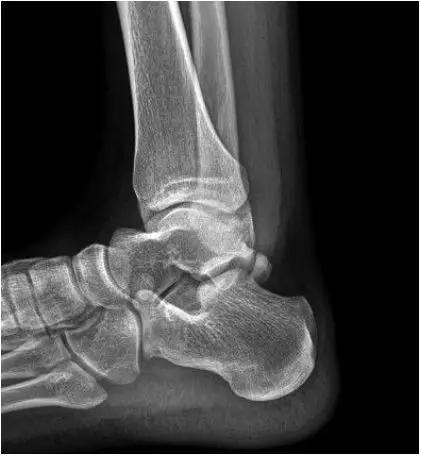

- 放射学表现主要为胫骨前下缘与距骨颈部前上缘鸟嘴样骨刺形成。

放射学表现主要为胫骨前下缘与距骨颈部前上缘鸟嘴样骨刺形成

- Ⅰ度:滑膜撞击,X线片显示有炎性反应,骨刺大小为3mm;

- Ⅱ度:骨软骨反应性骨赘>3mm;

- Ⅲ度:严重的外生骨赘,可伴有或不伴有碎裂, 在距骨背侧可见继发性骨赘,常伴有骨赘的碎裂;

- Ⅳ度:距骨和胫骨关节骨性关节炎改变。

- 踝关节正侧位X 线平片,侧位片均显示距骨后方有三角形或椭圆形的距后三角骨。部分病例伴有轻度的踝关节骨性关节病。